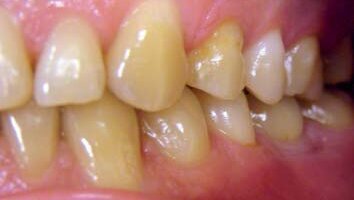

40-letni pacjent, zgłosił się w celu implantoprotetycznego uzupełnienia brakujących zębów 14, 36, 46. Był ogólnie zdrowy, nie stwierdzono przeciwwskazań do leczenia implantoprotetycznego.

Rozpoznano: grupę II wg Majewskiego, grupę A3 wg Eichnera, a wg Galasińskiej-Landsbergerowej – klasę II zarówno w szczęce, jak i w żuchwie. W badaniu klinicznym wykazano nieprawidłowości, które w sposób istotny mogłyby wpłynąć na końcowy efekt leczenia i wymagały przygotowania ortodontycznego przed przystąpieniem do docelowej rekonstrukcji implantoprotetycznej. Pacjent został skierowany na konsultację do ortodonty, gdzie stwierdzono przedwczesną utratę zębów 14, 36, 46, zgryz urazowy tet-a-tet na 12, 42, szparowatość wtórną między 43 i 44 oraz 33 i 34, mezjoinklinację 15, 37, 47, asymetrię łuku górnego i dolnego, pogłębienie zgryzu, stłoczenie dolnych siekaczy niewielkiego stopnia oraz spłaszczenie kształtu łuku dolnego.

Pacjent zaakceptował estetykę wykonanych implantokoron i końcowy efekt leczenia.